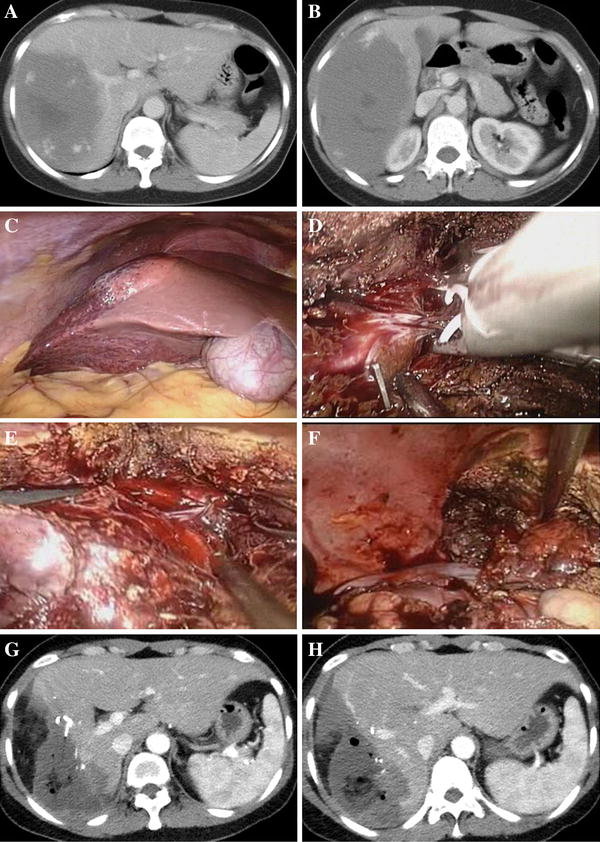

A cirurgia é recomendada na maioria dos casos sintomáticos, seja por ressecção ou enucleação. Essas técnicas podem ser realizadas por videolaparoscopia com menor tempo de internação, dor e sangramento, e a decisão da técnica depende da experiência do cirurgião, do número, tamanho e localização dos hemangiomas.